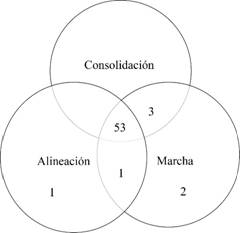

Definimos como éxito aquellos casos que presentaron alineación, consolidación total y marcha independiente con zapato comercial (51 casos, 85%) y fracasos funcionales aquellos con sinostosis funcional, no consolidación, alineación parcial, que no lograron marcha independiente y presentaron reactivación (nueve casos, 15%) (Tabla 1,Figuras 4 y 5).